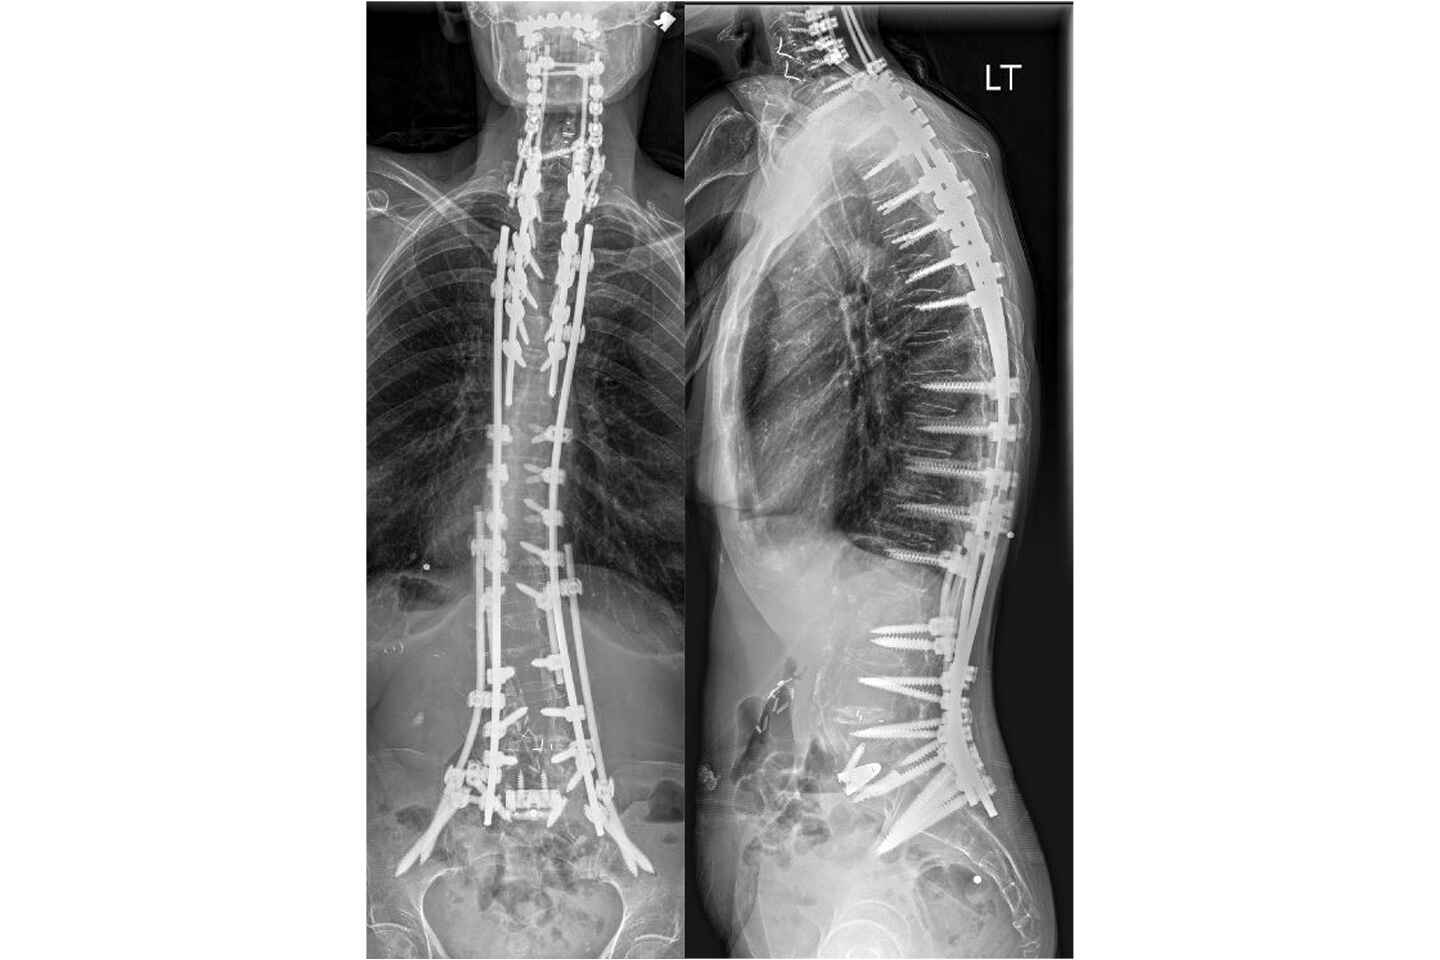

X-rays taken three months postoperatively showing resolution of the spinal deformity. Source: NYU Langone Health